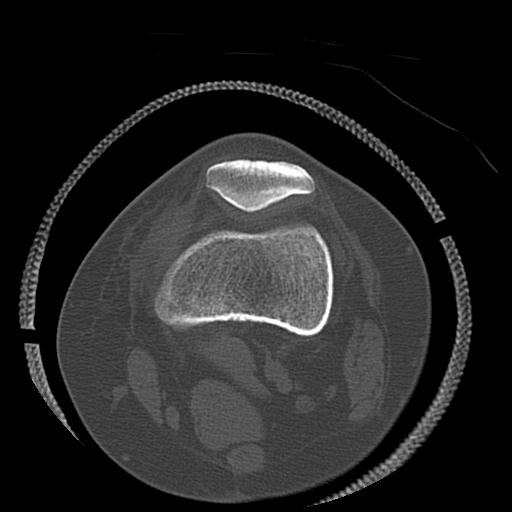

102803 1/12(キウスなし) 1/27 左下腿 4R 30歳女性 左脛骨軸内釘